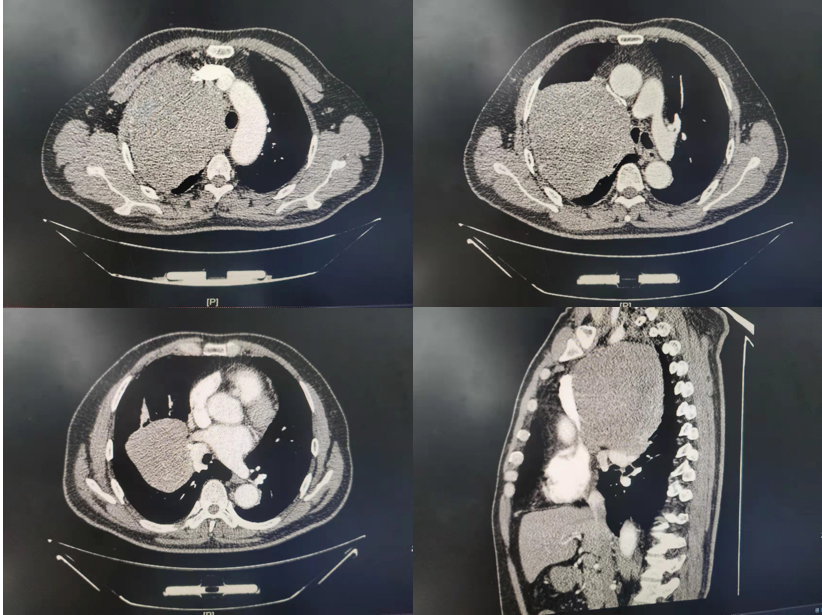

手术团队 患者孔某,男性,55岁,4年前出现气短症状,以躺卧时明显,坐立或站起时气短缓解。1个月前在当地医院行胸部CT检查示纵隔巨大占位性病变,大小约17cm*20cm,形如一颗小哈蜜瓜,呼吸困难。期间就诊于省内多家医院,均被告知无法手术,心灰意冷间辗转至辽宁省肿瘤医院就诊,得到手术治疗的建议后,患者表示对生活充满了希望。 影像资料 患者入院后胸外科三病区立即组织院内多学科会诊,由王伟主任带领专家组充分评估病情,考虑为巨大胸腺瘤,无名静脉、腔静脉及肺等周围组织受压明显,但考虑肿物膨胀生长可能性大,心肺功能无手术禁忌,且胸外科有丰富的大血管置换经验,在制定了详细的手术方案并准备了包括人工血管等完备的手术耗材后,于2022年2月22日由张亮主任医师作为主刀医生,童伟医生、韩天赐医生及张晨雷医生作为助手,在麻醉师张勇和手术室护士吕莉和王禹翔的配合下对患者实施了手术。手术采取左侧卧位经右胸入路,术中发现纵隔巨大肿物血运及其丰富,且肿物占据患者整个右侧胸腔的3/4,气管受压向健侧移位明显,在张亮医生轻柔细致的解剖下,发现肿物与术前评估一致,确为膨胀性生长,未见主要血管的严重侵犯,精细解剖肿物与主要血管及肺等重要组织的间隙后,顺利将肿物切除。 切除的巨大肿物 患者和张亮医生合影 患者术后病情平稳,恢复良好,患者及家属表示非常满意。术后病理回报为:符合孤立性纤维性肿物,细胞增生活跃。纵隔肿瘤是指在纵隔内生长的肿瘤,除了食管、气管、支气管和心脏生长的肿瘤。由于纵隔肿物常无明显临床症状,不易引起患者注意,常在体检时发现,或当肿瘤压迫重要组织器官出现相应的临床症状才来就诊。此次纵隔巨大肿物的成功切除,不仅显示出医院胸外科对疾病精准的判断,更加彰显了医院胸外科超高的手术技艺。